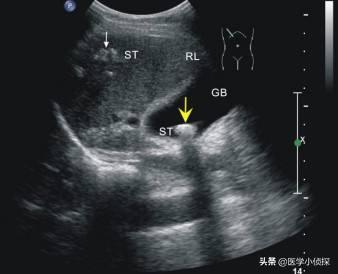

胆囊到底是一个什么样的器官?胆囊,其实就像大家买的一种类似古代钱袋子一样的囊性器官,长10-15cm,宽3-5cm,容量为40-60ml。

胆囊的上方是我们的肝脏,下方为十二指肠及横结肠,左侧为幽门,右侧为结肠右曲,前方为腹前壁。

而整个胆囊分为底、体、颈、管四个部分,其中体部位于胆囊底与颈部之间,伸缩性比较大,但颈部弯曲而且细,位置较深,其起始部膨大,形成Hartmann,大多数的胆囊结石就停留于此囊中。

而胆囊,我刚刚已经说过了,它是一个储存胆汁的器官,像一个可以收口的钱袋子一样,正常的话里边存的是胆汁,而胆囊壁一般有2mm那么厚,而且平时基本上都是光滑的,但是假如我们在这个胆囊壁上看到有一个突起一些的肉揪揪,用现在医学来讲,我们就叫它息肉!

所以,所谓的胆囊息肉,其实无非就是一种从大家的胆囊壁上向胆囊腔里边生长的一种实性的一个肉凸起,大小从几毫米到几厘米不等!